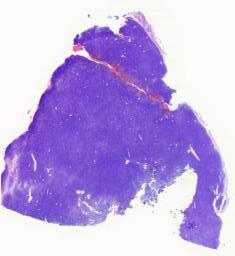

大体所见: 送检固定后脑组织一块,色灰白,质地略韧,大小约10×6.5×3.5cm,切面局部见皮层及白质分界欠清。